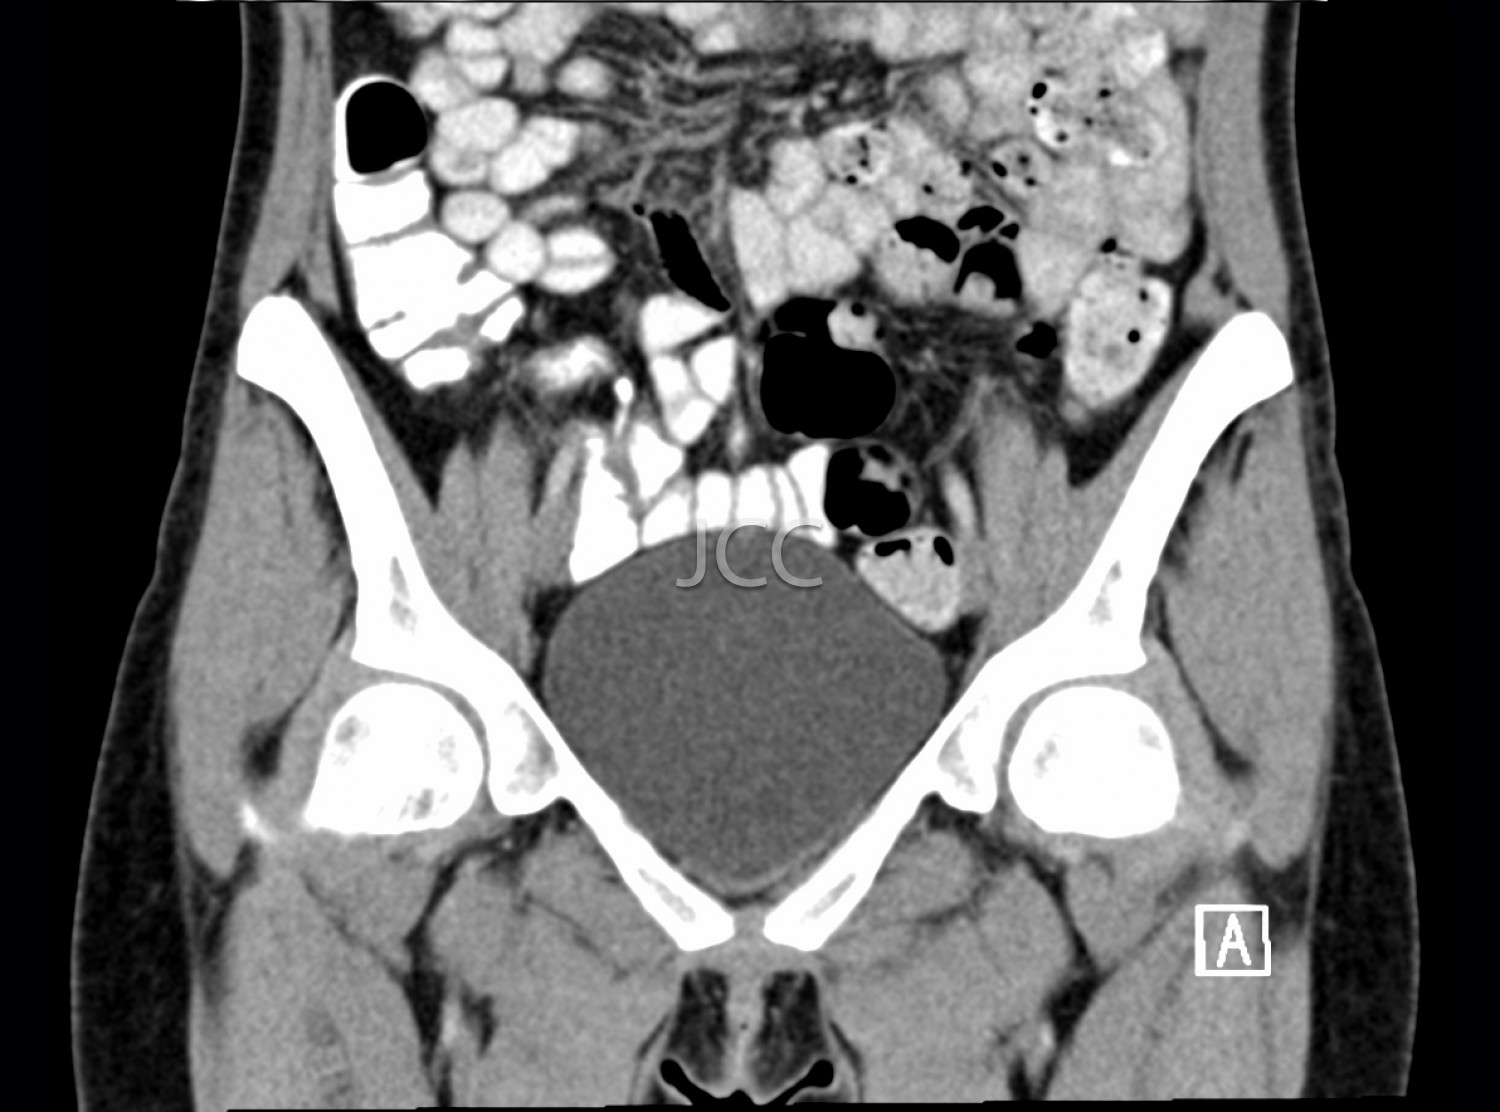

Computed Axial Tomography - Pelvis CAT scan

Computed Axial Tomography (CAT) - Dual Energy- 256 slices is a diagnostic technique that allows the evaluation of various parts of the human body, including the lungs, liver, pancreas, kidneys, heart, vascular structures and bone structures.